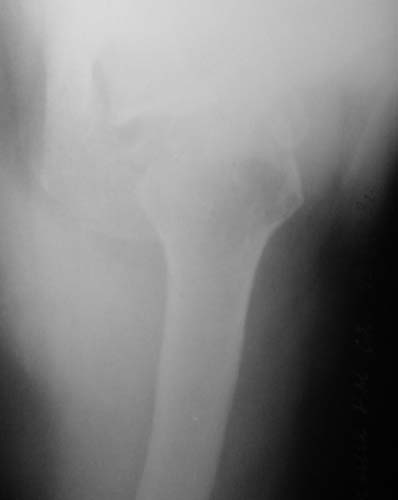

1

2

"Прицельная" съемка малопонятного очага.

1. На рентгене - нижний подвывих плеча и очаг остеолиза суставного бугорка с четкими контурами (вдавленный перелом на фоне остеопороза ? доброкачественная опухоль? аваскулярный некроз ? (хотя ни разу не слышал об аваскулярном некрозе плеча..)

Судя по снимкам, речь идTт о типичном случае Hill-Sachs Lesion. По этому поводу я позволю себе некоторый экскурс:

97 % всех вывихов плеча происходит по механизму комбинации отведения, разгибания и наружной ротации (А. Гринспан). В момент вывиха головка плеча ударяет о нижний край гленоида, что ведет к вдавленному или компрессионному перелому одной или обеих структур. Чаще всего, однако, повреждение возникает в задней латеральной области головки плечевой кости на переходе от головки к шейке. Этот диагноз можно выставить на основании рентгеновского снимка в переднезадней проекции с внутренней ротацией плеча. Несколько реже видно повреждение гленоида о передненижний перелом края. То, что мы называем Bankart Lesion. Это повреждение видно на ре. снимке в п.з. проекции при нейтральной позиции плеча. Разумеется хрящевые и мягкотканные повреждения (в смысле Банкарт) мы увидим лучше всего на ЯМР.